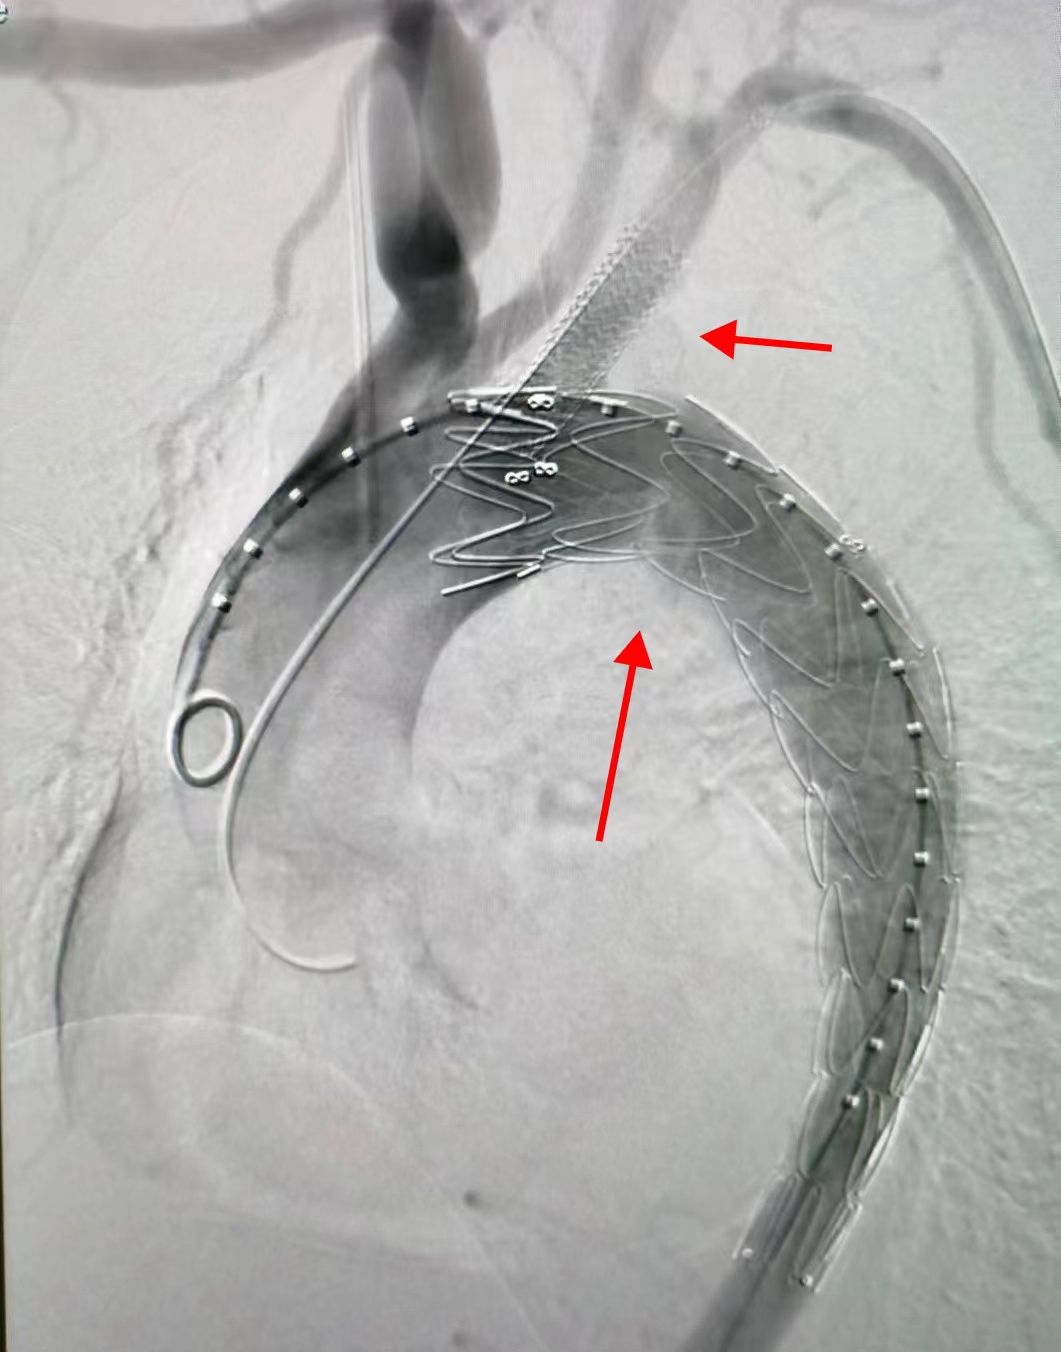

制定好周密的治療方案后,錢海云帶領(lǐng)團(tuán)隊(duì)僅用1小時(shí)為患者成功實(shí)施了主動(dòng)脈覆膜支架置入術(shù)+鎖骨下動(dòng)脈重建術(shù)。

經(jīng)股動(dòng)脈血管成功將覆膜支架植入患者胸主動(dòng)脈以閉合夾層破口。同時(shí)準(zhǔn)確定位左鎖骨下動(dòng)脈開口并植入一根平行支架。多角度定位后,支架順利釋放,至此主動(dòng)脈破口得到完全封堵,主動(dòng)脈真腔及左鎖骨下動(dòng)脈重建完畢。術(shù)后,王女士恢復(fù)良好,第二天已經(jīng)能夠正常下床活動(dòng)。

置入支架